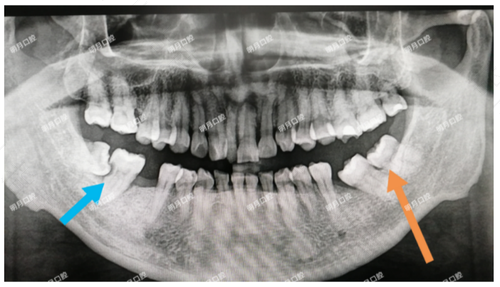

镶牙之前,需要拍片检查。在选择假牙之前,也要了解清楚假牙的种类。目前,假牙分为固定假牙和活动假牙。如果拔掉的牙齿数量少,缺牙区域前后有稳固的牙齿并且牙齿健康,可以考虑选择装固定义齿。固定义齿的功能几乎和真牙差不多。如果觉得装固定义齿贵,也可以考虑装活动假牙。活动假牙具有美观、易清洁的特点。